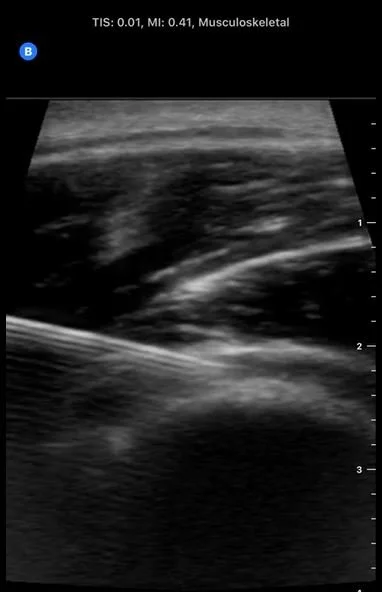

For diagnostic purposes, ultrasound offers real-time, high-resolution imaging of muscles, tendons, ligaments, joints, nerves, and other soft tissues, enabling dynamic assessment and facilitating the identification of structural abnormalities, acute injuries, and chronic overuse conditions with the advantages of portability, safety, and cost-effectiveness compared to other imaging modalities.

Interventional sports ultrasound, as endorsed by the American Medical Society for Sports Medicine, is used to guide procedures such as aspirations, diagnostic and therapeutic injections, tenotomies, releases, and hydrodissections, with strong evidence supporting its superior accuracy and moderate evidence for improved efficacy and cost-effectiveness over landmark-guided techniques.